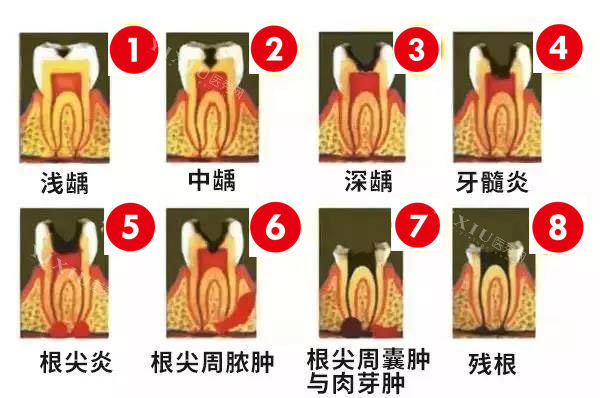

技术特点:该机构在牙齿修复方面经验充足,提供多种修复方案。对于常见的牙齿问题,如龋齿、牙周炎等,能够给出合理的治疗建议。设备维护良好,操作规范。